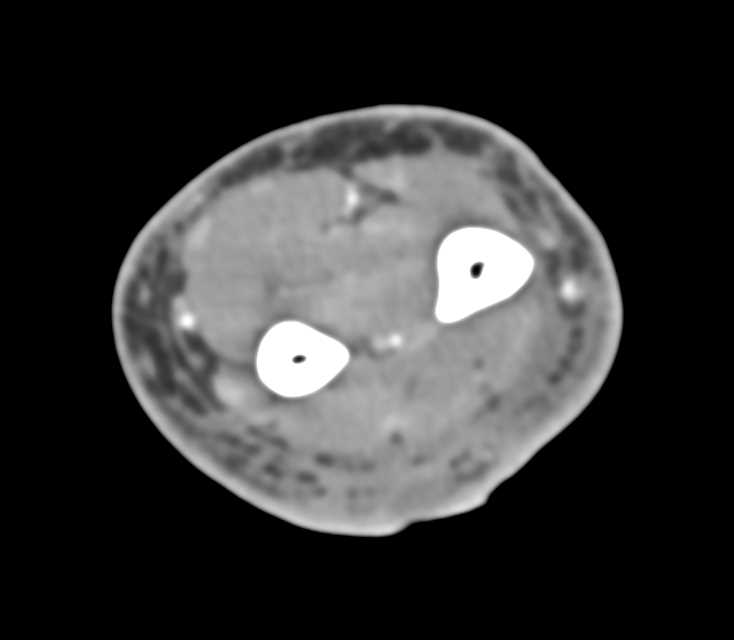

Metastatic Renal Cell Carcinoma to Muscle